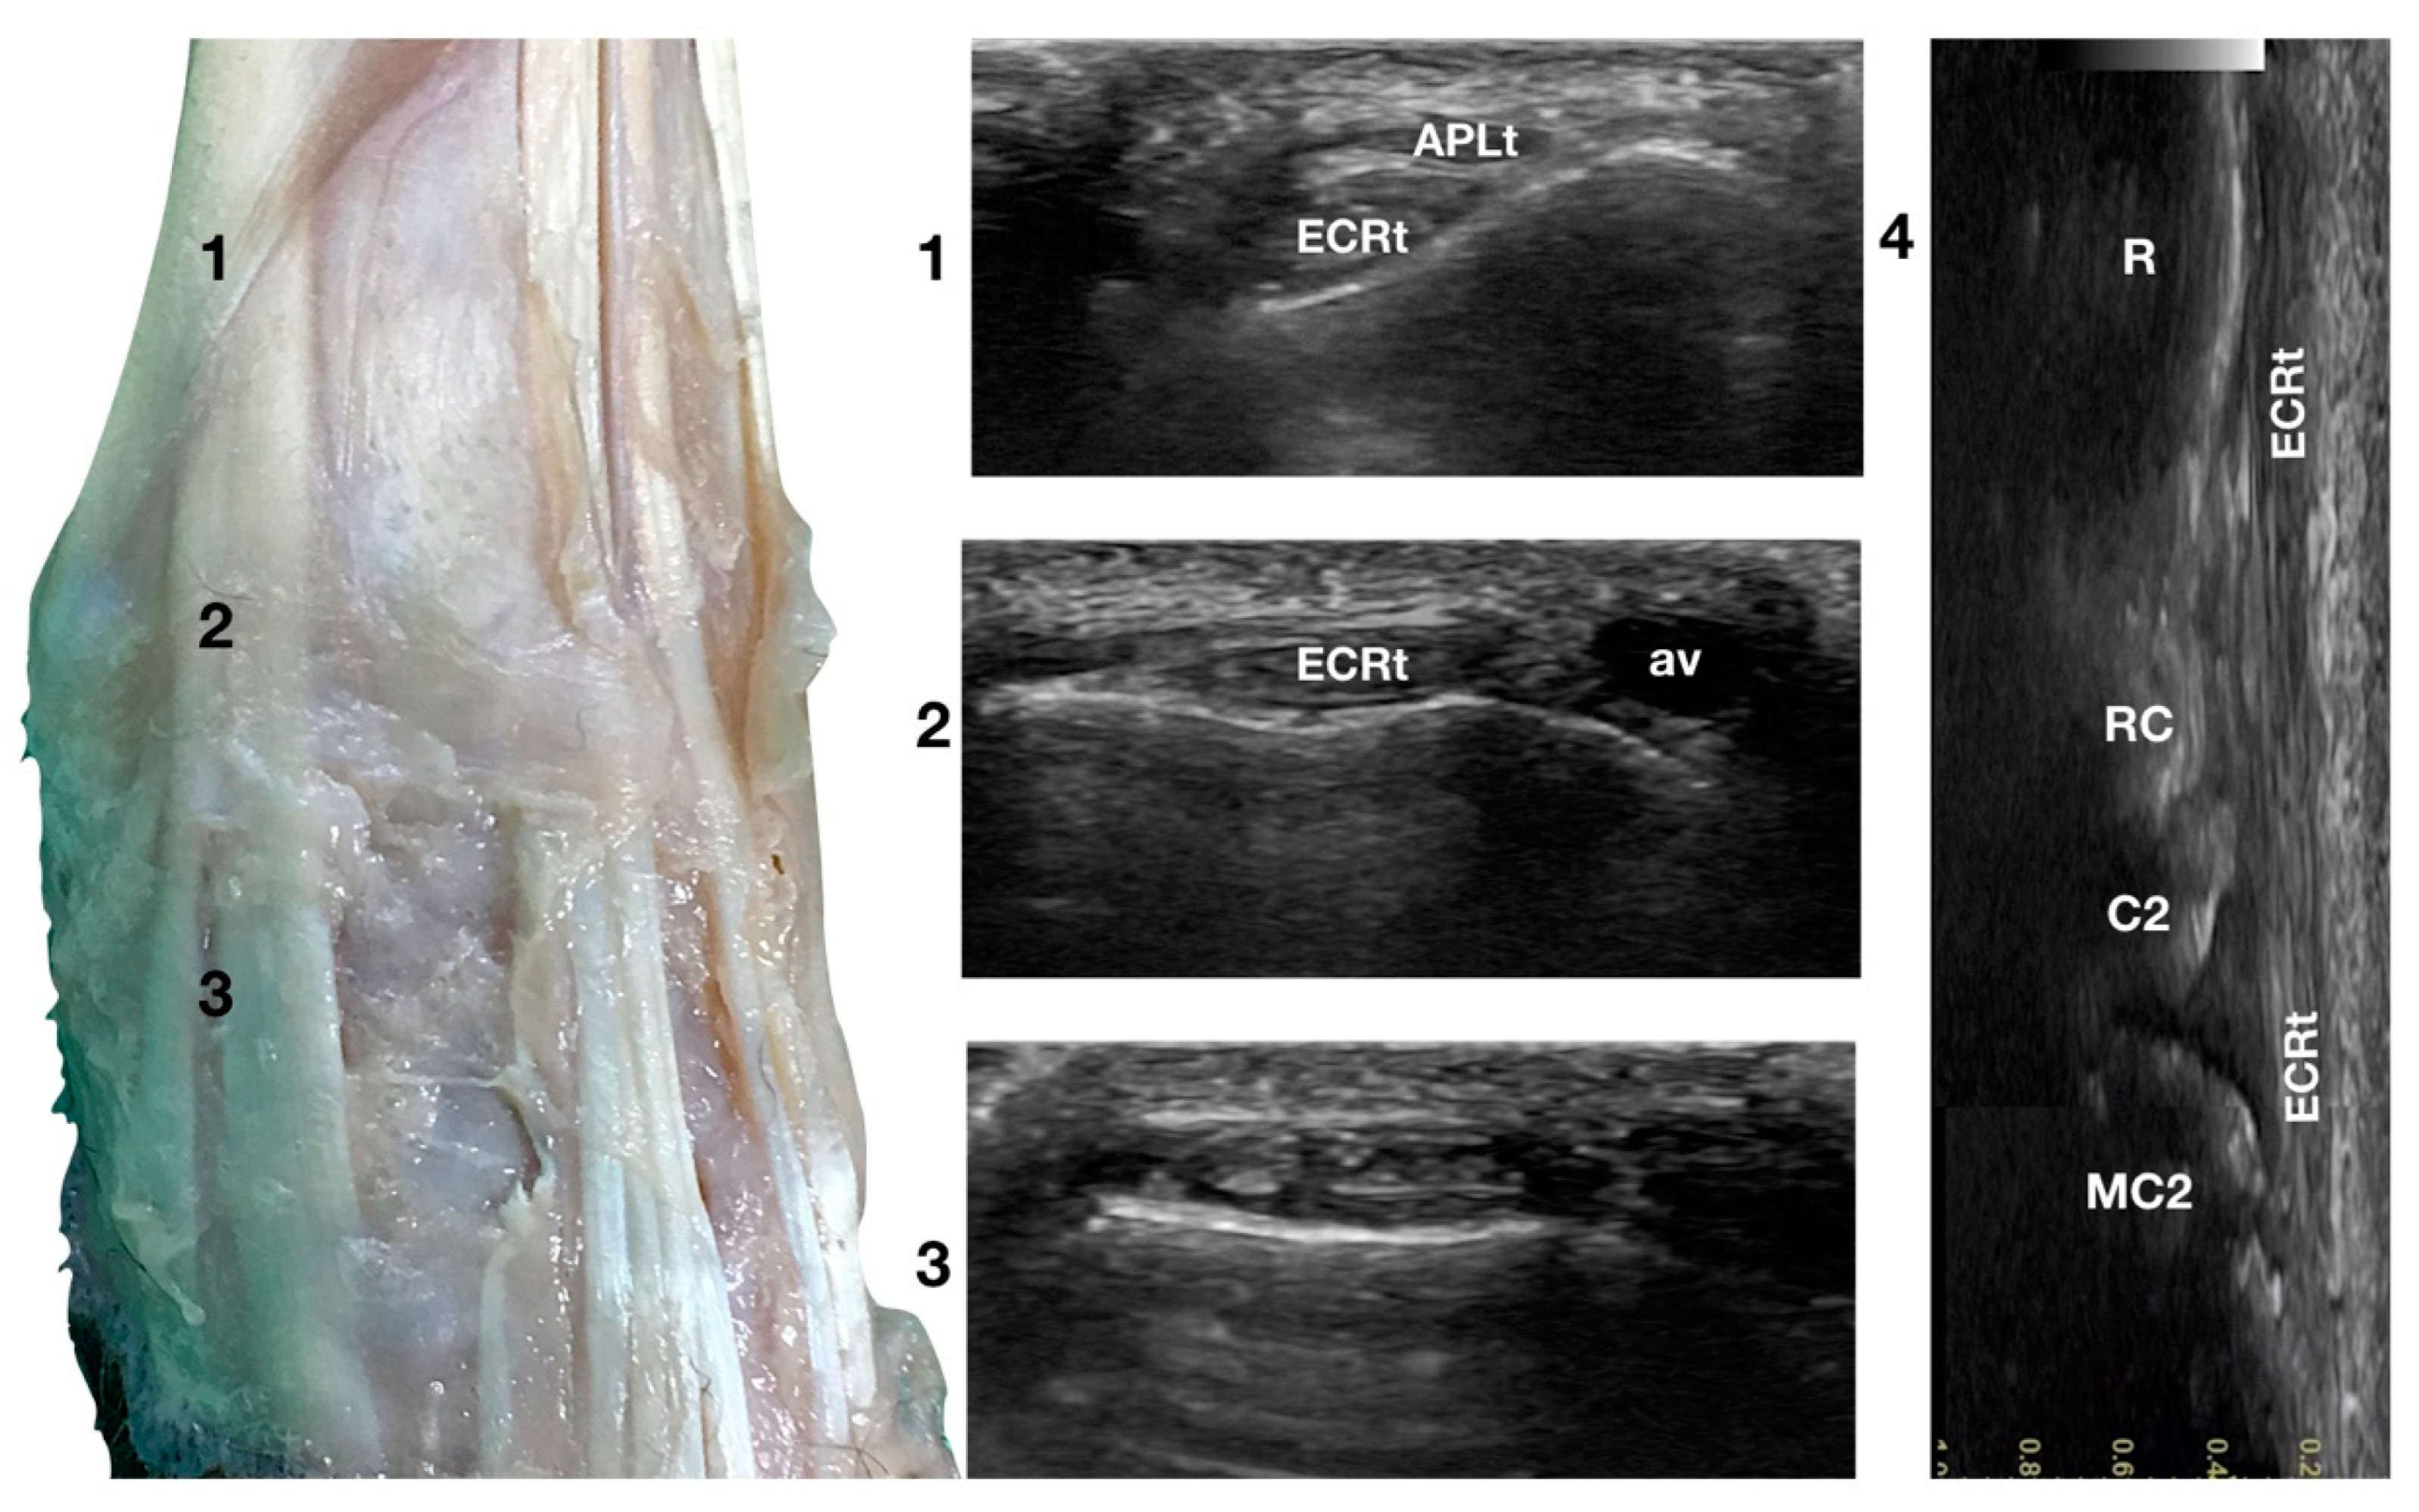

3.1.1. Extensor Carpi Radialis Tendon (ECRt) Ultrasonographic Anatomy

The ulnar notch of the radius was palpated with the thumb and used as a starting point to assess the dorsal structures of the carpus (Figure 1a). The tendons of all the faces were measured at this level in transverse and longitudinal scan planes. Immediately dorsally to the easily recognisable ulnar notch, the Abductor Pollicis Longus tendon (APLt) (only minimally perceptible) was palpated. The adjacent, more dorsal, more profound and easier to recognise groove of the Extensor Carpi Radialis tendon (ECRt) was felt immediately after. At this level, the ECRt was thick, round, and minimally movable, and an easy start for the systematic carpal evaluation. The probe was in a transverse scan plane, starting at the ulnar notch level. The tendon was ultrasonographically well defined by the surrounding tissues due to the thin hyperechoic line, which enhanced the contour (peritendineum) and the minimal fluid accumulation in the surrounding fibrous tendon sheath (Figure 2).

Figure 2.

Dorsal carpal face centred on the Extensor Carpi Radialis tendon. At point 1, the APL superficial and thin emerging tendon covers the thick tendon of the ECR. At the ulnar notch of the radius (2), the ECR tendon is easily recognised due to the thick hyperechoic layer that defines its contour (peritendineum). Medial to the tendon, the accessory cephalic vein (av) is visible. At the intercarpal joint (3), the tendon subdivides into the smaller medial part and the more significant lateral part, as is easily seen in the image. However, they are still enclosed in the same tendon sheath that completely divides into two tendons distally. Image 4 is the visualisation of the longitudinal image of the medial portion of the ECRt. The bony surface beneath is recognisable. R, radius; RC, radiocarpal bone; C2, carpal bone two; MC2, second metacarpal bone.

Sliding the probe dorsally, the ECRt became thinner and closer to the bone, and the APLt and its tenomuscular junction were seen more superficially, obliquely crossing the path of the straight ECRt. At the ulnar notch level, the ECRt thickness reached the maximum, and was separated from the skin and the periosteal surface of the radius by a thick fascia and fat layer. Just distal to this level, the tendon flattened again and became wider, quickly assuming a horizontal figure eight shape, and subdividing into two parts: a thin medial tendon and a more prominent lateral tendon. At the intercarpal joint level, the two tendons split. The medial tendon (Extensor Carpi Radialis Longus) showed a narrow and rounded shape. It became thinner and less distinct distally until it ended at the base of the second metacarpal bone. This tendon was easier to follow distally when imaged on longitudinal view, obtained by rotating the probe clockwise by 90 degrees to have the proximal portion of the tendon to the left of the screen. The lateral part of the tendon (Extensor Carpi Radialis Brevis) was oval, flattened, and ended on the base of the third metacarpal bone. This tendon was easily followed distally in the longitudinal scan plane.

The tendons showed a linear, dense, and hyperechoic fibrillar pattern in the transverse and longitudinal planes. The two tendons showed a progressive reduction in their diameters; however, they broadened distally at the insertions. Carpometacarpal flexion aided the examination and allowed checking whether adhesion or subluxation of the tendon rather than deeper joint effusion or bone surface remodelling was present. Minimal synovial effusion (less than 1 mm in thickness) was often but not always seen in the radiocarpal and intercarpal joints and, less commonly, in the carpometacarpal joint. Lateral and superficial to the ECRt, the accessory cephalic vein was seen. The position of the vein could vary if too much pressure was applied to the probe.